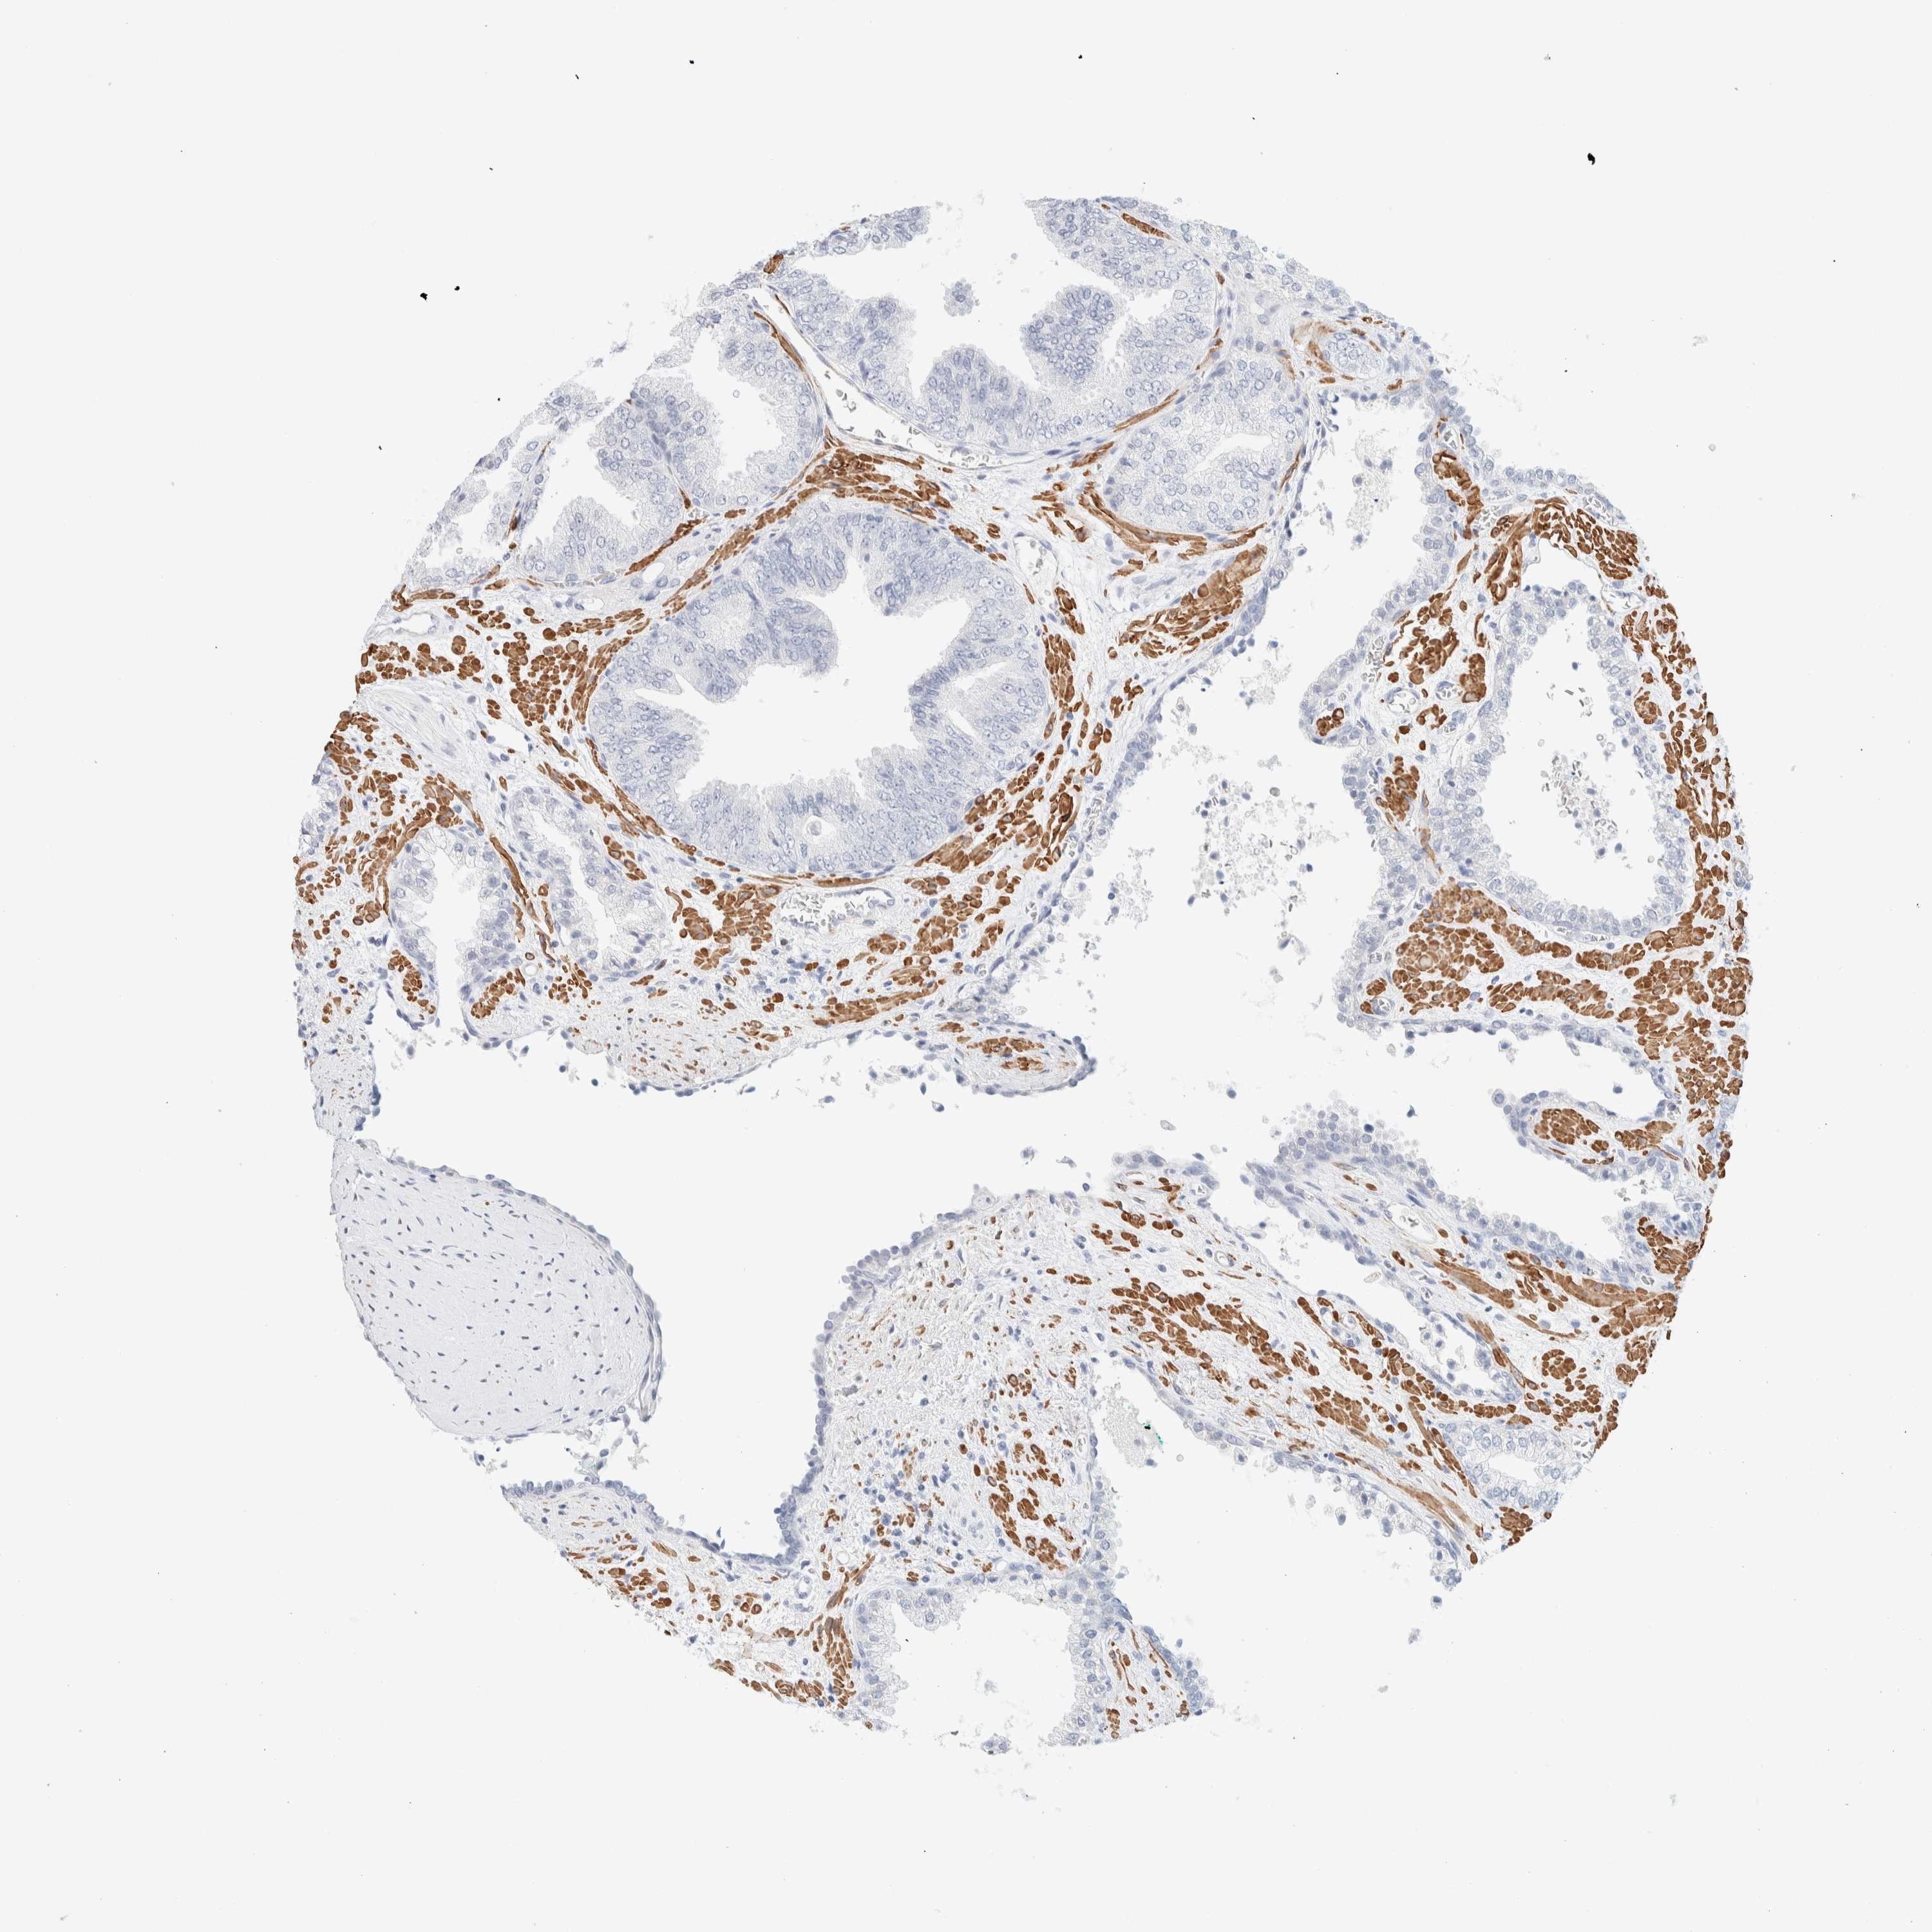

PROSTATE CANCER - Protein expressioni

A mouse-over function shows sample information and annotation data. Click on an image to view it in a full screen mode. Samples can be filtered based on level of antibody staining by selecting one or several of the following categories: high, medium, low and not detected. The assay and annotation is described here.

Note that samples used for immunohistochemistry by the Human Protein Atlas do not correspond to samples in the TCGA dataset.

Antibody stainingi

Antibody staining in the annotated cell types in the current human tissue is reported as not detected, low, medium, or high, based on conventional immunohistochemistry profiling in selected tissues. This score is based on the combination of the staining intensity and fraction of stained cells.

Each image is clickable and will lead to virtual microscopy that enables deeper exploration of all samples and also displays staining intensity scores, fraction scores and subcellular localization as well as patient and tissue information for each sample.

Antibody HPA023861

Antibody HPA026536

Staining

High

Medium

Low

Not detected

Intensity

Strong

Moderate

Weak

Negative

Quantity

>75%

75%-25%

<25%

None

Location

Nuclear

Cytoplasmic/membranous

Cytoplasmic/membranous,nuclear

Adenocarcinoma, High grade

Adenocarcinoma, Low grade